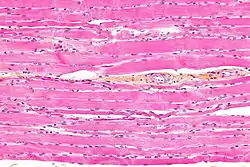

Micrograph of HPS stained skeletal striated muscle (fibularis longus).